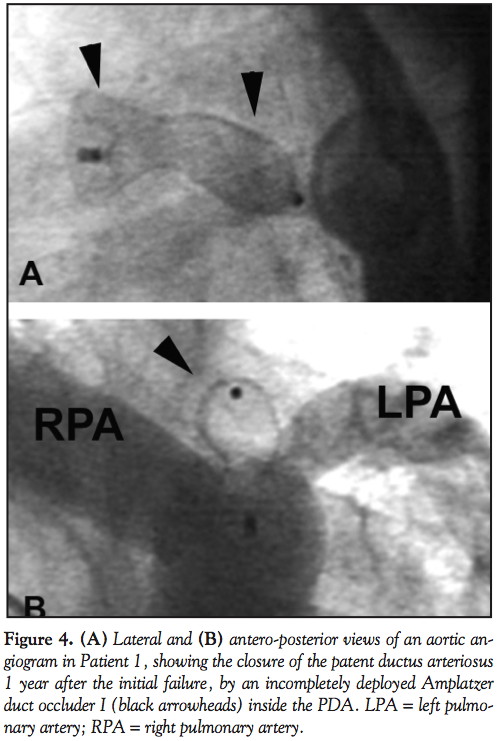

For the ADO I, immediate closure was achieved in 40% of the cases (30/74 patients), rising to 94.6% (70/74 patients) at 24 hours, and to 96% (71/74 patients) at 6 months. Thus, the ADO I failed to close the PDA in 3 patients. The first patient (Patient 1 in Table 2 and Figure 1) was a 3-year-old, 17 kg boy with a 4 mm type D PDA which was initially closed with an 8-6 ADO I. The Amplatzer asymptomatically migrated to the abdominal aorta before discharge from the hospital. The shunt seen on the follow-up serial echocardiograms was thought to

be a residual shunt, and the migration was diagnosed only 1 year later. We believe that this migration occurred on the second day, because the predischarge chest x-ray examined retrospectively 1 year later did not show the radio-opaque markers of the ADO in the usual position. The device was embedded asymptomatically in the abdominal aorta, facing the celiac artery (Figure 3A, black arrow). Attempts at its percutaneous removal 1 year later failed due to strong adhesions to the aortic wall; hence, it was left in place since it wasn’t obstructive. This failure was considered recovered, as the PDA was percutaneously closed using a 14-12 ADO I (Figure 3B); the device was oversized to achieve incomplete deployment of the aortic disc inside the PDA (Figure 4). The first ADO is still in the abdominal aorta with no gradient on the serial Doppler studies for 6 years now. The second patient (Patient 2 in Table 2 and Figure 1) was a 7-month-old who weighed 6.5 kg, with a 2.2-mm wide and 9-mm long type C PDA. When it was advanced and correctly positioned in the PDA, the 6-4 ADO I became severely kinked with a very narrow angle, and thus kept sliding backward and protruding into the pulmonary artery during every release attempt. The device wasn’t released, the procedure was abandoned, and the patient was referred for surgery 3 months later. This happened before the ADO II era. The third ADO I failure (Patient 3 in Table 2 and Figure 1) was a 6-month-old, 7 kg baby girl with a type B, 6.6 mm duct; the 10-8 ADO I totally obstructed the aortic flow and was retrieved before releasing. The patient was also referred for surgery.

Interestingly, all 3 recovered failures were attributed to migration of the device, and all 3 definite failures referred to surgery were due to the protrusion of the device, and obstruction of the aorta or pulmonary artery. Concerning migration, one may assume that if an ADO is completely deployed, secondary migration should be obviously due to the small size of the device relative to the diameter of the PDA; this assumption was confirmed in our series by the successful secondary occlusion of the ducts using larger devices in all 3 patients. The patient illustrating best the advantages of device oversizing was Patient 1. In this patient, the measured minimal diameter of the 20-mm long type D PDA was around 4 mm. An 8-6 ADO I was placed in the aortic restriction, which resulted in the migration of the device. This failure was recovered by modifying the deployment technique of the ADO I; the device was oversized on purpose (14-12 ADO I), to obtain an incomplete deployment of the aortic disc inside the duct. The excessive length of this PDA prevented protrusion of the device into the pulmonary artery after its release.3 This technique was successfully reiterated in other patients with type C ducts measuring more than 5 mm. However, care must be taken with device oversizing; generous oversizing may tear the duct wall. Oversizing needs also a small restriction area somewhere in the duct. In a 30 kg, 14-year-old patient with severe pulmonary hypertension and a short type A PDA, the ADO I was largely oversized, but normally deployed, so that the pulmonary narrowing transformed the pulmonary part of the device in a retention disc. This prevented aortic migration of the ADO that might have been facilitated by pulmonary hypertension. This technique is not applicable in small infants.